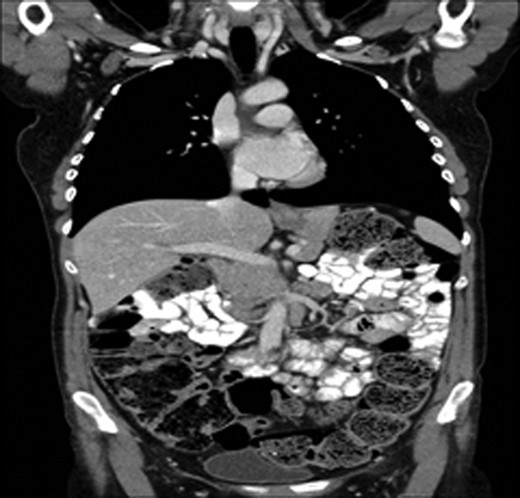

A 43-year-old female, 10 weeks postpartum, underwent colonoscopy for bleeding per rectum showing a bulky tumour (Fig. 1) in the rectum at 5 cm. Histologically poorly differentiated adenocarcinoma of the rectum (Fig. 2) T3N1Mo. Underwent laparoscopic loop ileostomy formation for impending bowel obstruction. Bloods showed Hemoglobin13.6 g/dL, Bilirubin 10umol/L, CEA 3.6 ng/mL. MRI pelvis (Fig. 3a and b) showed locally advanced annular neoplasm of mid and upper rectum. CT TAP (Fig. 4) reported no distant metastasis. She had neoadjuvant chemoradiothreapy with poor response. Post chemotherapy she noticed a lump in her right breast and axilla. Breast mammogram (Fig. 5a) showed 26 mm lesion in the right breast at 10 o'clock position and ultrasound showed 27 mm lesion in right axilla. Core biopsy (Fig. 6) reported signet ring morphology. The tumour stained positive with CK20, CDX-2 and CEA. There was no staining with CK7, ER, PR or Her-2. The rectal biopsy specimen, also analysed for KRAS status, was KRAS/NRAS/BRAF negative. She is being followed up by oncology with FOLFOX+Panitumumab.